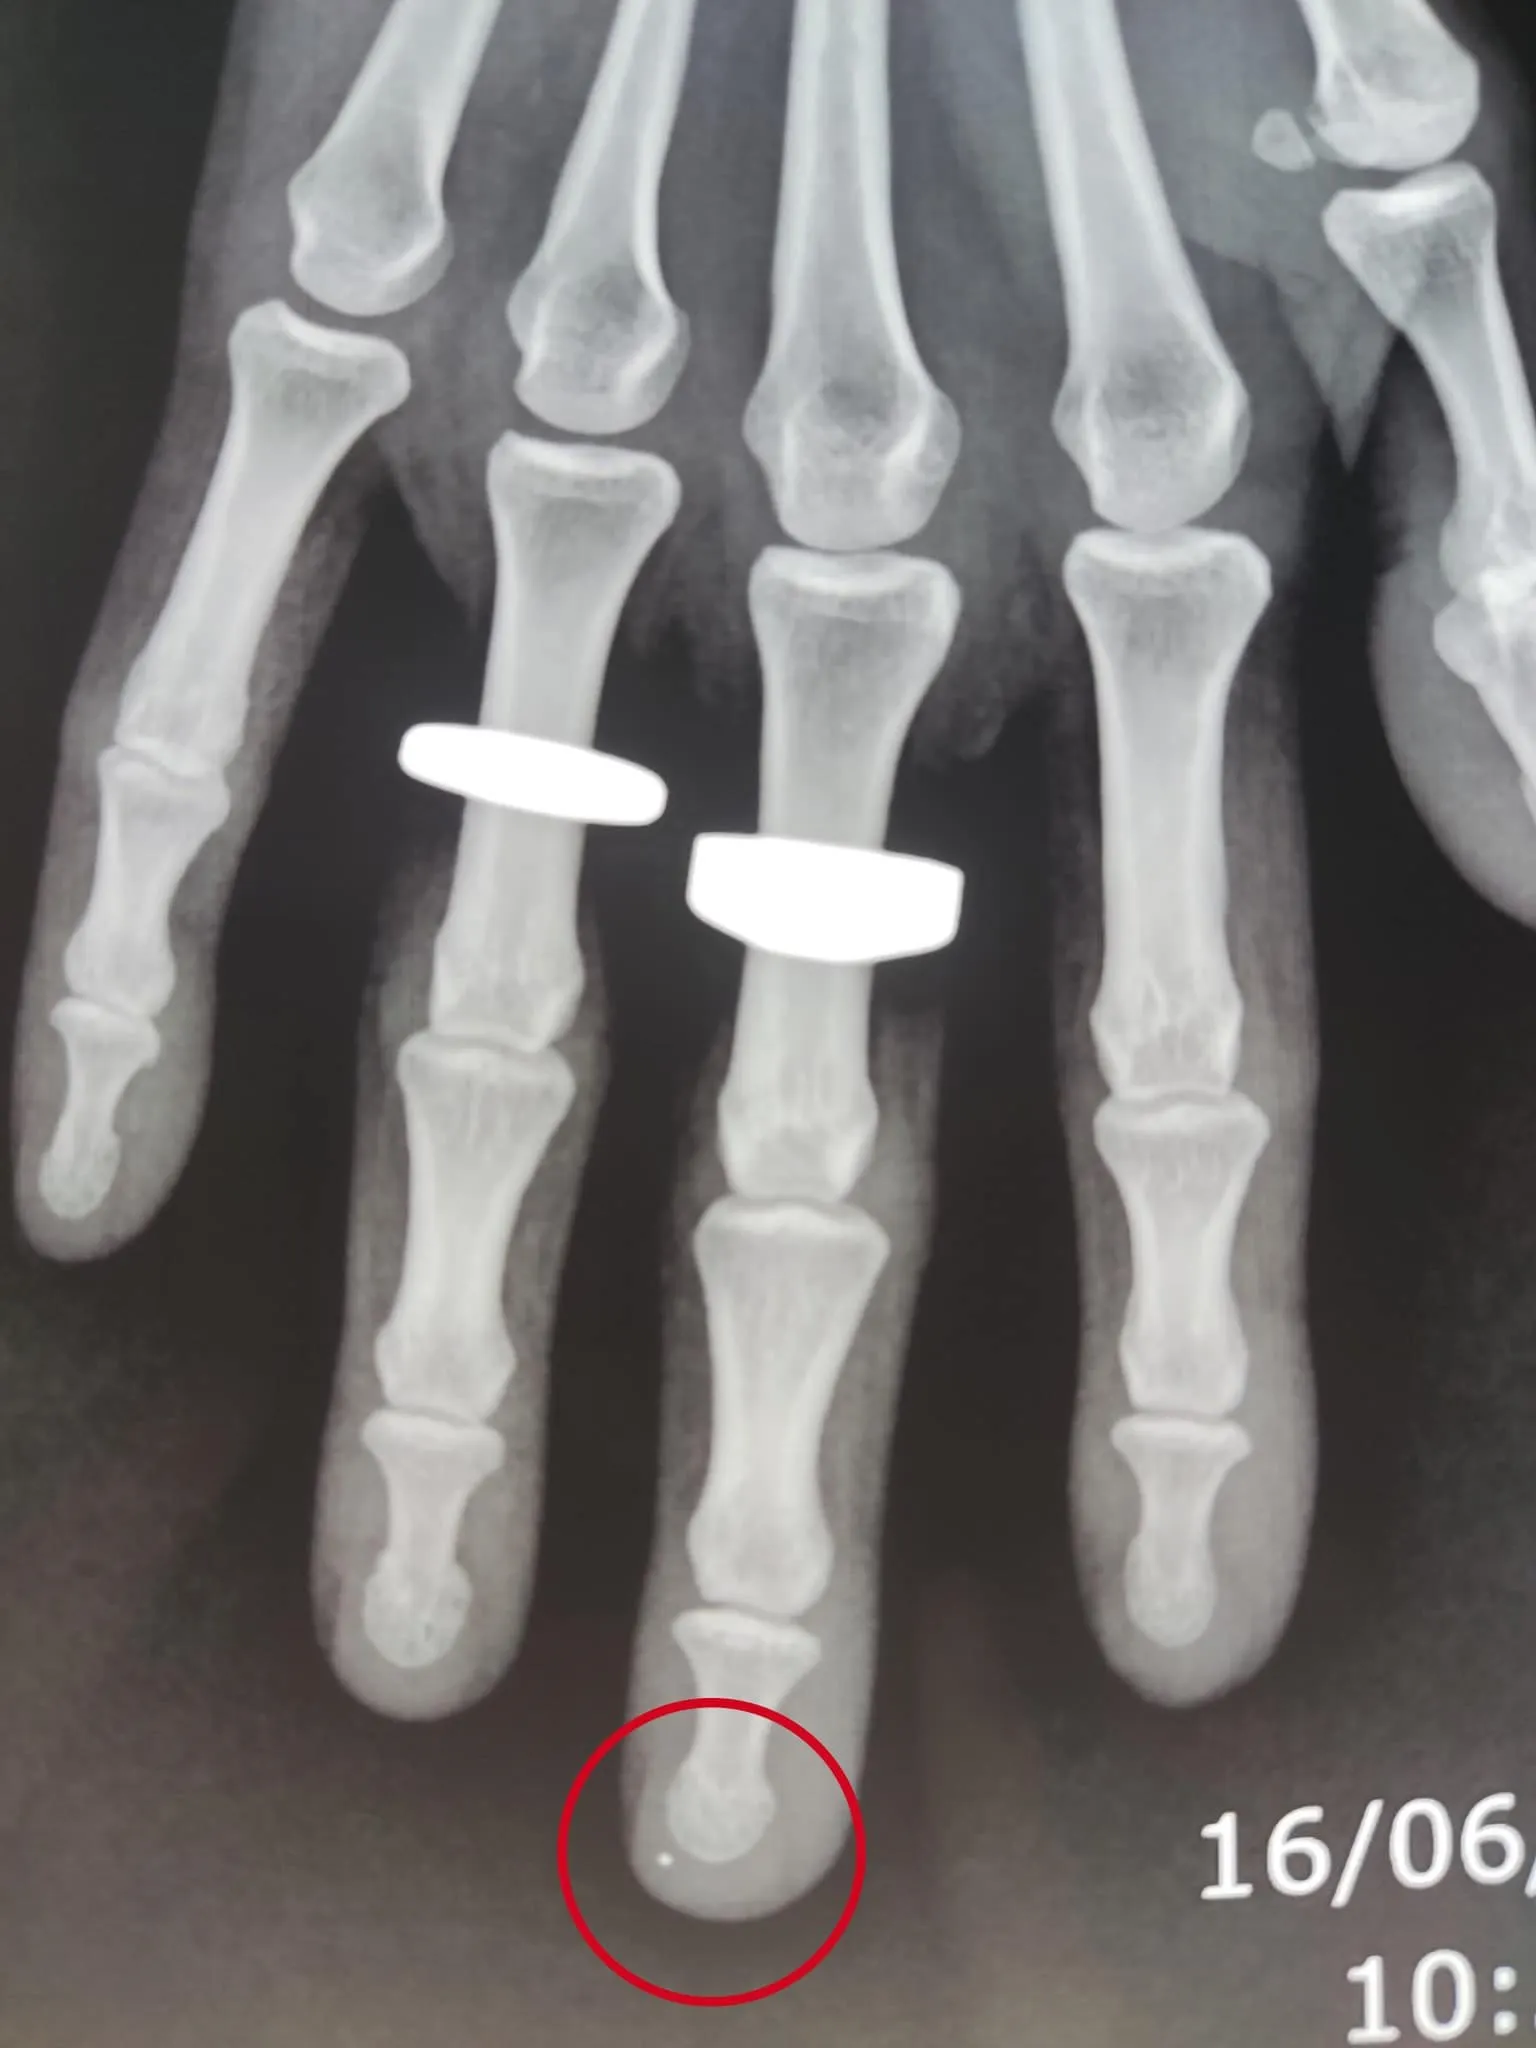

Theo đó, được biết đây là trường hợp một nữ công nhân bị mũi kim khâu đâm vào xuyên qua ngón tay trong quá trình lao động. Hình ảnh X-quang cho thấy còn một mảnh dị vật kim khí rất nhỏ trong ngón tay khả năng là đầu kim gãy. Các bác sĩ đã chẩn đoán đây là trường hợp nguy hiểm và đã phẫu thuật cấp cứu lấy dị vật.

Ảnh X-quang chụp xương bàn tay bị kim khâu đâm

Bác sĩ Cao Anh Thái cho biết quá trình phẫu thuật khá khó khăn vì dị vật quá nhỏ, ở vị trí khá khó tiếp cận. Ngoài ra còn có nguy cơ dị vật dễ di chuyển trong quá trình thao tác. Một trong những điều nguy hiểm đe dọa tính mạng bệnh nhân khiến bác sĩ cần phẫu thuật sớm là vì các biến chứng nguy hiểm do đầu kim dễ di chuyển đến bất cứ nơi nào trong cơ thể.